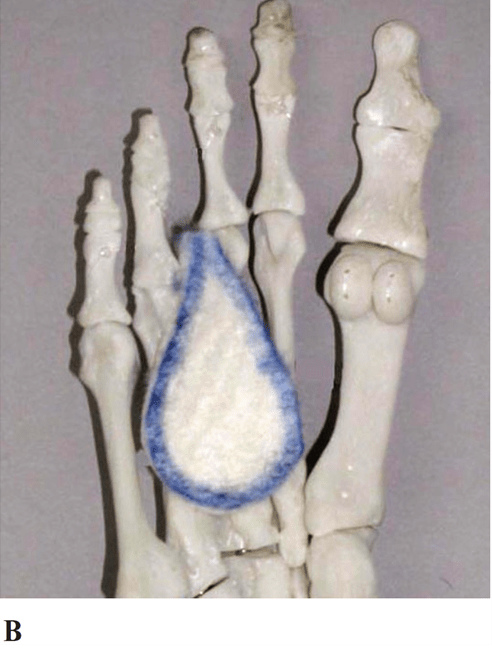

This tape job treats treats a strain/sprain to the medial or lateral longitudinal arches, cuboid subluxation and plantar fasciitis. Three words in the name.

Teardrop Arch Tape

This item would help support your foot if you had Morton's Neuroma. Two words in the name.

Teardrop Pad